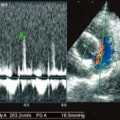

A:超音波カラードップラーでの僧帽弁逆流速度の測定

B:E波とA波の測定

C:僧帽弁逆流の動画(大きく表示させたい場合は、ココをクリックして下さい。)